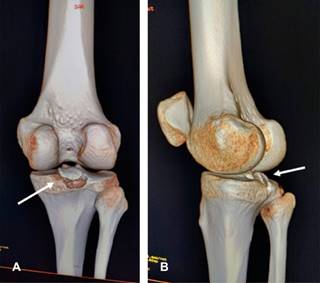

La fractura por avulsión del ligamento cruzado posterior (LCP) representa la lesión aislada más común del LCP (~ 50%), implicando la separación de la inserción tibial posterior del LCP en grados variables. Estos traumatismos se observan comúnmente en accidentes de motocicleta o automovilísticos (lesiones en Tableros de instrumentos) en los que se producen fuerzas de posteriorización contra la tibia en una rodilla flexionada. También se observan en individuos que saltan y aterrizan sobre un pie en flexión plantar mientras la rodilla está flexionada, en el contexto deportivo (esencialmente colocando la tibia bajo una fuerza de posteriorización). Se les clasifica en tipo I: cuando el fragmento óseo no está desplazado; tipo II: existe desplazamiento hacia arriba de la cara posterior del fragmento de hueso tibial avulsionado; y tipo III: cuando el fragmento óseo avulsionado está totalmente desplazado. Clínicamente existe signo del cajón posterior. Radiográficamente, en la placa lateral se identifica discontinuidad ósea en la superficie articular tibial posterior (Figura 1). En la resonancia magnética o la tomografía computarizada, se puede observar un fragmento de hueso fracturado unido al LCP retraído (Figura 2). El diagnóstico diferencial incluye desgarro del LCP. El tratamiento es la reinserción quirúrgica del fragmento avulsionado (Figura 3).

Figura 2: Imágenes de reconstrucción 3D de tomografía computarizada de rodilla derecha. A) Vista posterior, desplazamiento superior de fragmento óseo que corresponde a fractura avulsión del ligamento cruzado posterior. B) Vista oblicua, muestra la misma lesión (flechas).